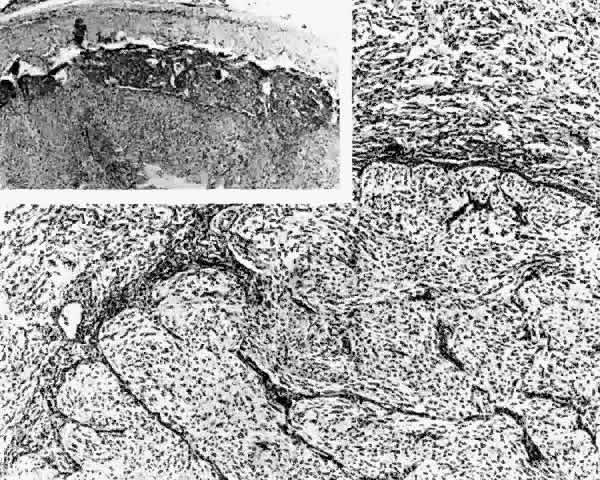

Gross examination of optic nerve gliomas usually reveals a smooth, fusiform, intradural enlargement of the optic nerve (Fig. 6). After extending through the optic canal in a dumbbell fashion, there may be extension to posterior structures.4 Most optic gliomas are classified as juvenile pilocytic astrocytomas and have a benign histologic appearance. Pilocytic refers to the spindle-shaped astrocytes with elongated nuclei that are often arranged in a parallel fashion (Fig. 7). Oligodendroglial cells may be scattered throughout the glioma. These tumors can contain carrot- or cigar-shaped eosinophilic astrocytic cytoplasmic inclusions known as Rosenthal fibers4 (Fig. 8). Microcystoid extracellular spaces containing acid mucopolysaccharide generated by mucin-producing astrocytes are often seen.85 Less common features can include capillary hyperplasia, mitotic figures, tissue necrosis with hemorrhage,86 and glial giant cells.4

Fig. 7. Photomicrograph of an optic nerve glioma, demonstrating a mixture of pilocytic astrocytes and some oligodendro-glial cells.

Fig. 8. Optic nerve glioma. The numerous carrot-shaped or cigar-shaped dark bodies are called Rosenthal fibers (Verhoeff's bodies). (H & E, × 176; Courtesy of Drs. Eggers, Jakobiec, and Jones)

The histopathologic features of a chiasmal glioma are almost identical to those of an optic nerve glioma. Because the normal optic chiasm lacks the connective tissue septae found in the normal optic nerve, these septae are not found in chiasmal glioma specimens.71 A reactive leptomeningeal hyperplasia may surround gliomas, leading to an erroneous biopsy interpretation of meningioma23 (Fig. 9). In contrast to schwannomas and neurofibromas, which are positive for the intermediate filament vimentin, immunohistochemical analysis of cytoplasmic glial intermediate filaments in pilocytic astrocytomas reveals positive staining for glial fibrillary acidic protein.87

Fig. 9. Optic nerve glioma. Optic nerve (below) has been replaced by proliferating astrocytes. Tumor cells (above) fill the distended subdural space (H & E, × 63) Inset. Arachnoidal hyperplasia where the nerve inserts into the globe. (H & E, × 25; Courtesy of Drs. Eggers, Jakobiec, and Jones)